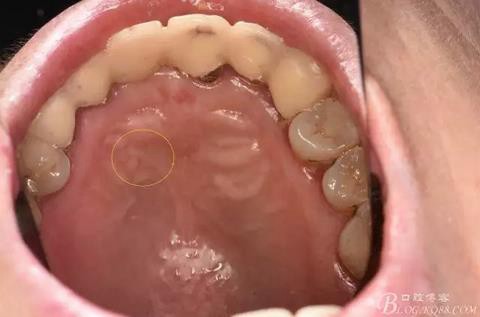

圖4.腭側(cè)觀:12根尖正對的腭粘膜隆起、有波動感